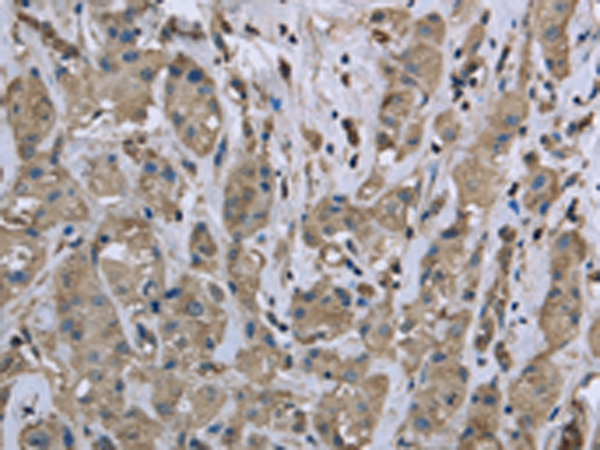

分类: 科研抗体货号: P08296别名: HSCO; YF13H12应用: WB,IHC反应种属: Human, Mouse